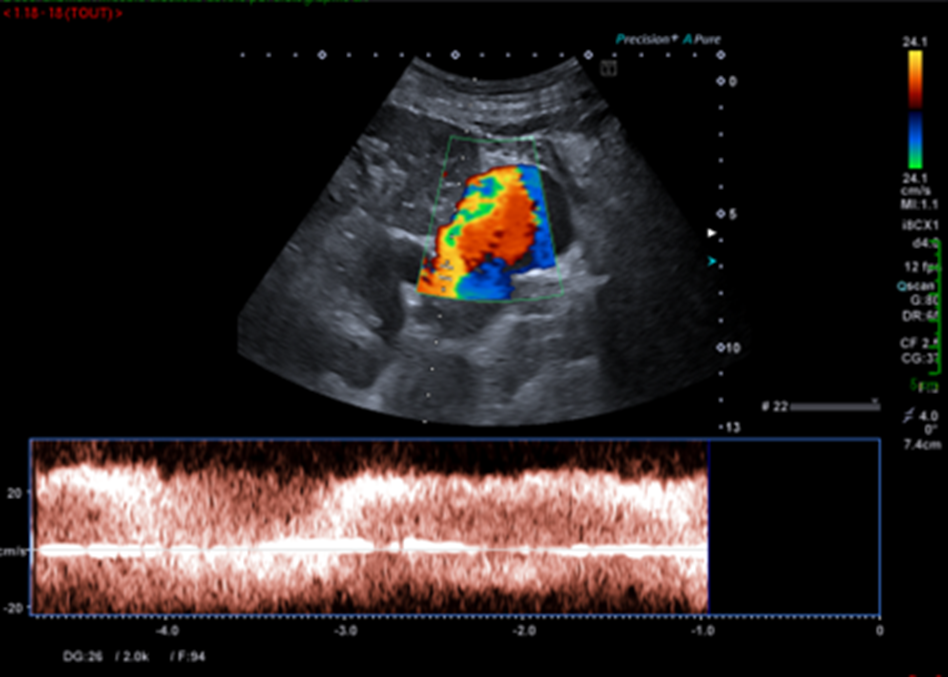

Voici le résumé des balayages et réglages réalisés par le manipulateur en échographie.

Ces nouvelles coupes (faisant apparaitre la rate, le doppler couleur et le doppler pulsé), montrent alors non pas un kyste rénal mais des volumineuses veines péri spléniques correspondant à des voies de dérivations spléno-rénales témoignant d’une hypertension portale probablement liée à la cirrhose sous-jacente.

Il est donc nécessaire de compléter son examen par une recherche d’autres signes d’hypertension portale notamment la présence d’ascite ou toute autre dérivation veineuse digestive (recanalisation de la VO, varices porto-portales, dilatation de la VMS et/ou dilatation des veines gastriques, varices mésentérique-caves (difficilement visibles en échographie-Doppler) ou la présence de varices porto-caves).